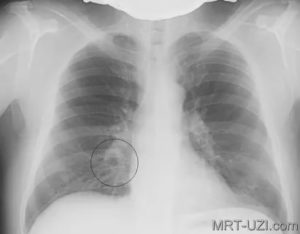

Рентген грудной клетки у детей. Очаговая пневмония.Рентген грудной клетки у детей. Очаговая пневмония.

Снимок при очаговой пневмонии

Крупозная пневмония – гиперергическое воспаление, которое проходит следующие стадии: прилив, красное и серое опеченение и период разрешения.

На снимках видно, что воспалительный процесс локализуется лобарно или сублобарно (то есть поражается доля легкого) с вовлечением плевры. Легочный рисунок при этом изменяется, а легочные корни расширяются. Видны застои жидкости в плевральной полости. С течением болезни тени на снимках становятся темнее.